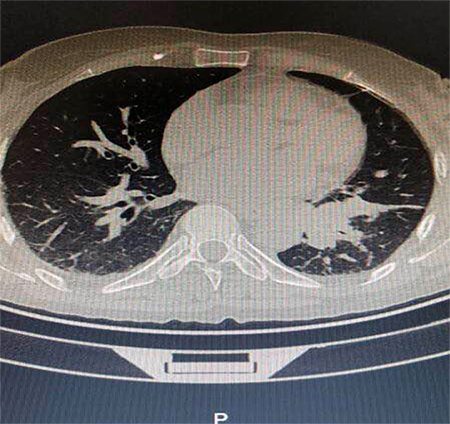

海宁的吴女士(化名)因胸闷、咳嗽久不见好转,进行了胸部CT检查,结果在肺部发现了35px的结节,并且不排除肺癌可能。

知道结果的吴女士十分担心,有医生建议先进行手术比较保险,但王剑飞认为应先进一步确诊,不着急手术。后经过一段时间的消炎、雾化吸入、中药调理等治疗,一个月后,吴女士的结节缩小至6mm,一切症状都显示并没有癌变危险,保持三个月随访即可。这令吴女士安了心,也免除了手术的痛苦。

故事二、肺部磨玻璃结节别纠结

徐先生(化名)被查出肺部磨玻璃结节已有数月,且有三个——最大的约7mm,最小的5mm左右。自此,他陷入了惶惶不安,四处寻医,遍查医典,掌握了十分丰富的与肺部结节相关的医学知识。但他还是无法作出决定——开刀,或不开刀?

后经过王剑飞的一番分析与开导,徐先生终于决定手术,术后诊断——最大的是微浸润癌,其余2个是原位癌。虽然从预后看,开刀早晚差别不大,但徐先生终于安心了,又能轻松面对生活了。而对于王剑飞能想病人所想,细心考虑每一个患者的顾虑,徐先生感到十分暖心及感激。